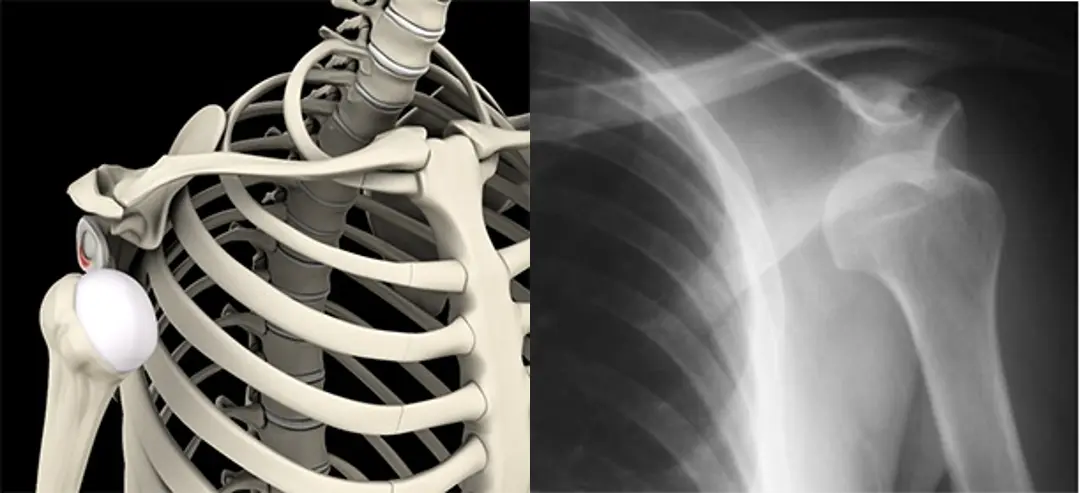

Η βασική άρθρωση του ώμου αποτελείται από την κεφαλής του βραχιονίου (σφαιρική επιφάνεια) και την ωμογλήνη (κοίλη επιφάνεια), ενώ αποτελεί την άρθρωση του σώματος που εξαρθρώνεται σε μεγαλύτερο βαθμό. Η άρθρωση του ώμου είναι σχεδιασμένη ώστε να επιτρέπει ένα μεγάλο εύρος κινήσεων. Συνεπώς είναι απαραίτητη η υποστήριξη της από τους συνδέσμους και τους μύες που την περιβάλλουν.

Όταν ο ώμος μας εξαρθρώνεται, η κεφαλή του βραχιονίου μετατοπίζεται εκτός της κοίλης αρθρικής επιφάνειας της ωμογλήνης.

Το εξάρθρημα του ώμου χωρίζεται σε πρόσθιο και οπίσθιο. Ο πιο συχνός τύπος (96-98%) είναι το πρόσθιο όπου η κεφαλή μετατοπίζεται μπροστά και κάτω από την κοίλη επιφάνεια της ωμογλήνης. Το πρόσθιο εξάρθρημα του ώμου προκαλείται στην πλειονότητα των περιπτώσεων μετά από πτώση με το χέρι μας σε έκταση, απαγωγή και έξω στροφή. Το οπίσθιο εξάρθρημα αντιθέτως είναι συνήθως αποτέλεσμα μεγάλης βίας, όπως τα τροχαία ατυχήματα και οι επιληπτικές κρίσεις. Σε πιο σπάνιες περιπτώσεις, μπορεί να συμβεί ακόμα και με πολύ μικρή βία ή χωρίς κάποιο τραυματισμό, ειδικότερα στους ανθρώπους με χαλαρές αρθρώσεις. Σε αυτές τις περιπτώσεις ο ώμος μπορεί να εξαρθρωθεί κατά την διάρκεια του ύπνου ή από κάποια απότομη κίνηση, χωρίς όμως ο ασθενής να αντιληφθεί τον ακριβή τρόπο.